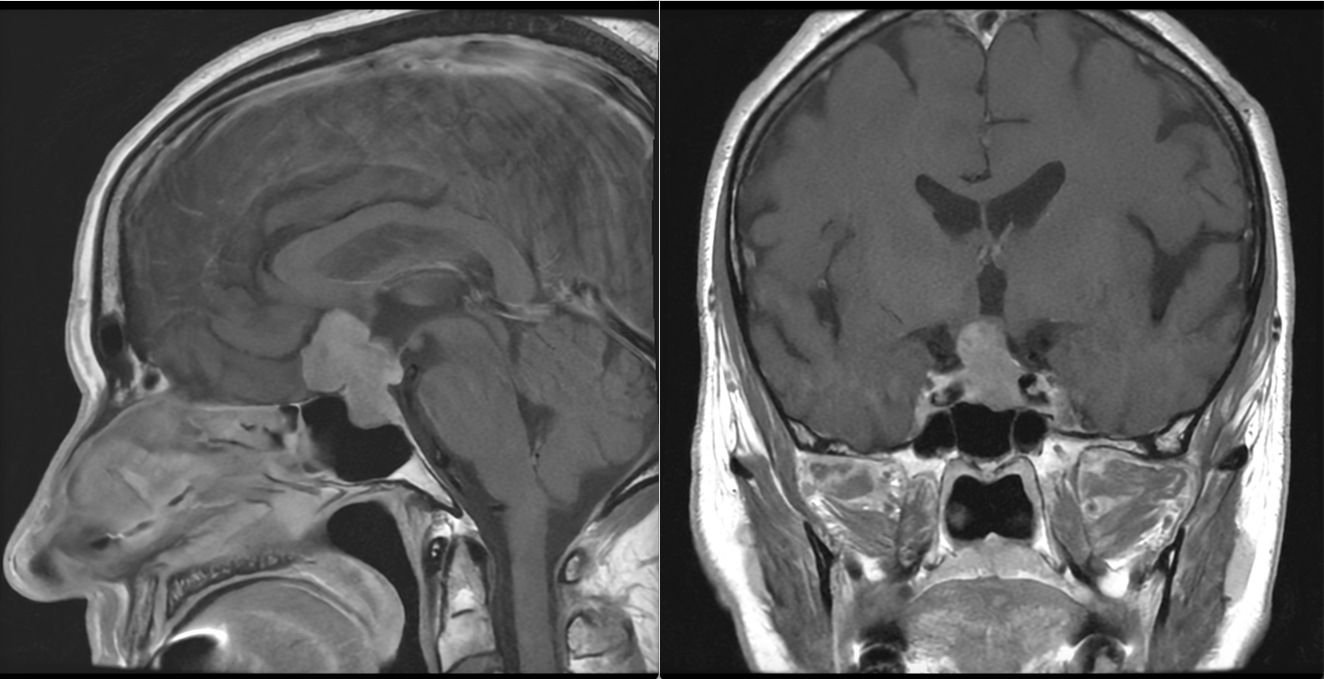

- Macroadenoamele hipofizare apar ca mase tumorale cu priza de contrast localizate la nivelul șeii turcești, eventual cu extensie superioară (supraselară) spre nervii optici sau, mai rar, inferioară, în sinusul sfenoid; de multe ori ele se pot extinde și lateral, în sinusurile cavernoase (structuri vasculare venoase formate în grosimea meningelui care mărginește lateral șaua turcească, prin care trec arterele carotide interne).

- Microadenoamele necesită un tip special de examinare RMN, cu secvențe repetate (în dinamică) realizate după administrarea substanței de contrast. Ele apar de obicei ca niște defecte de umplere – mici zone ne-gadolinofile (glanda hipofiză normală capteaza contrast mai repede decât adenomul); alteori singurul indiciu despre existența și localizarea adenomului (în afară de analizele hormonale) îl constituie asimetria glandei cu devierea tijei hipofizre de partea opusă